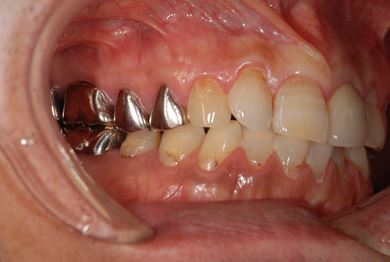

| 性別/年齢 | 男性 / 69歳 | ||||||||||||||||||||||||||||||||

| 主訴 | 1.左上奥歯の詰め物が取れた 2.左上前歯の欠け 3.右下奥歯の欠け | ||||||||||||||||||||||||||||||||

| 治療方針 | セラミック治療にて、審美的回復を行う。 | ||||||||||||||||||||||||||||||||

| 治療内容 | メタルボンドセラミッククラウン1本(メタルボンド用土台1本)、ハイブリッドセラミックインレー1本 | ||||||||||||||||||||||||||||||||